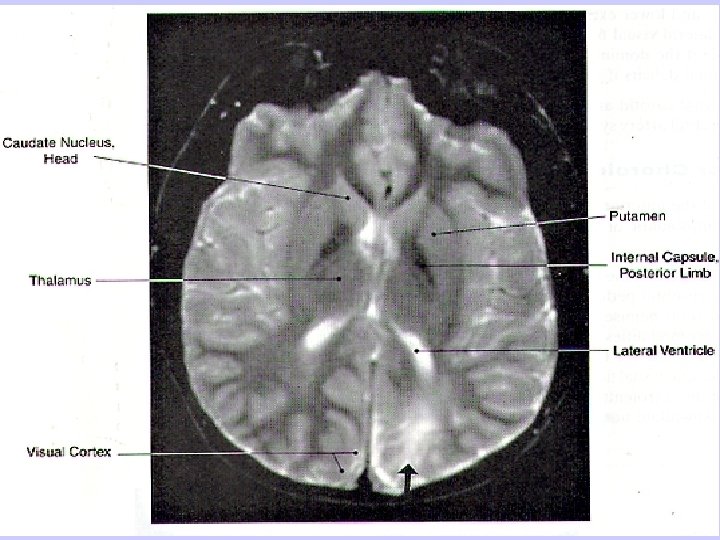

Small caliber lenticulostriate arteries, branches of the middle cerebral artery, supply most of the internal capsule.

Capsular hemiplegia- involving genu (corticobulbars) and post. limb (corticospinals) of the internal capsule (MCA)

Lenticulostriate Artery Syndrome Infarction in the territory of the lenticulostriate artery, a branch of the middle cerebral artery, is associated with pure motor hemiplegia because of involvement of the internal capsule.